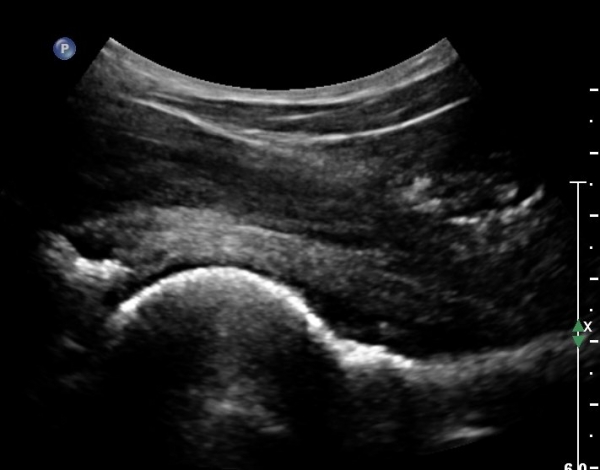

ÃÊÀ½ÆÄ°Ë»ç: °í°üÀý ¾ÕÂÊ Á¾´Ü¸é °Ë»ç¿¡¼­ °üÀý³¶ÀÌ µÎ²¨¿öÁö°í °æ¹ÌÇÑ °üÀý³» ºÎÁ¾À» º¸ÀÓ(»çÁø1, 2)